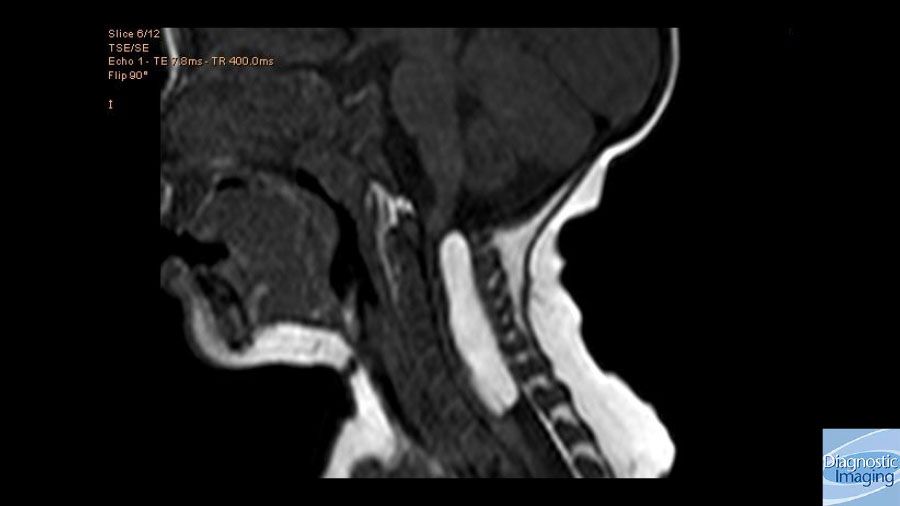

Case History: 8-year-old male with neck pain and right upper limb weakness for two months.

Case History: 8-year-old male presented with neck pain and right upper limb weakness for two months.